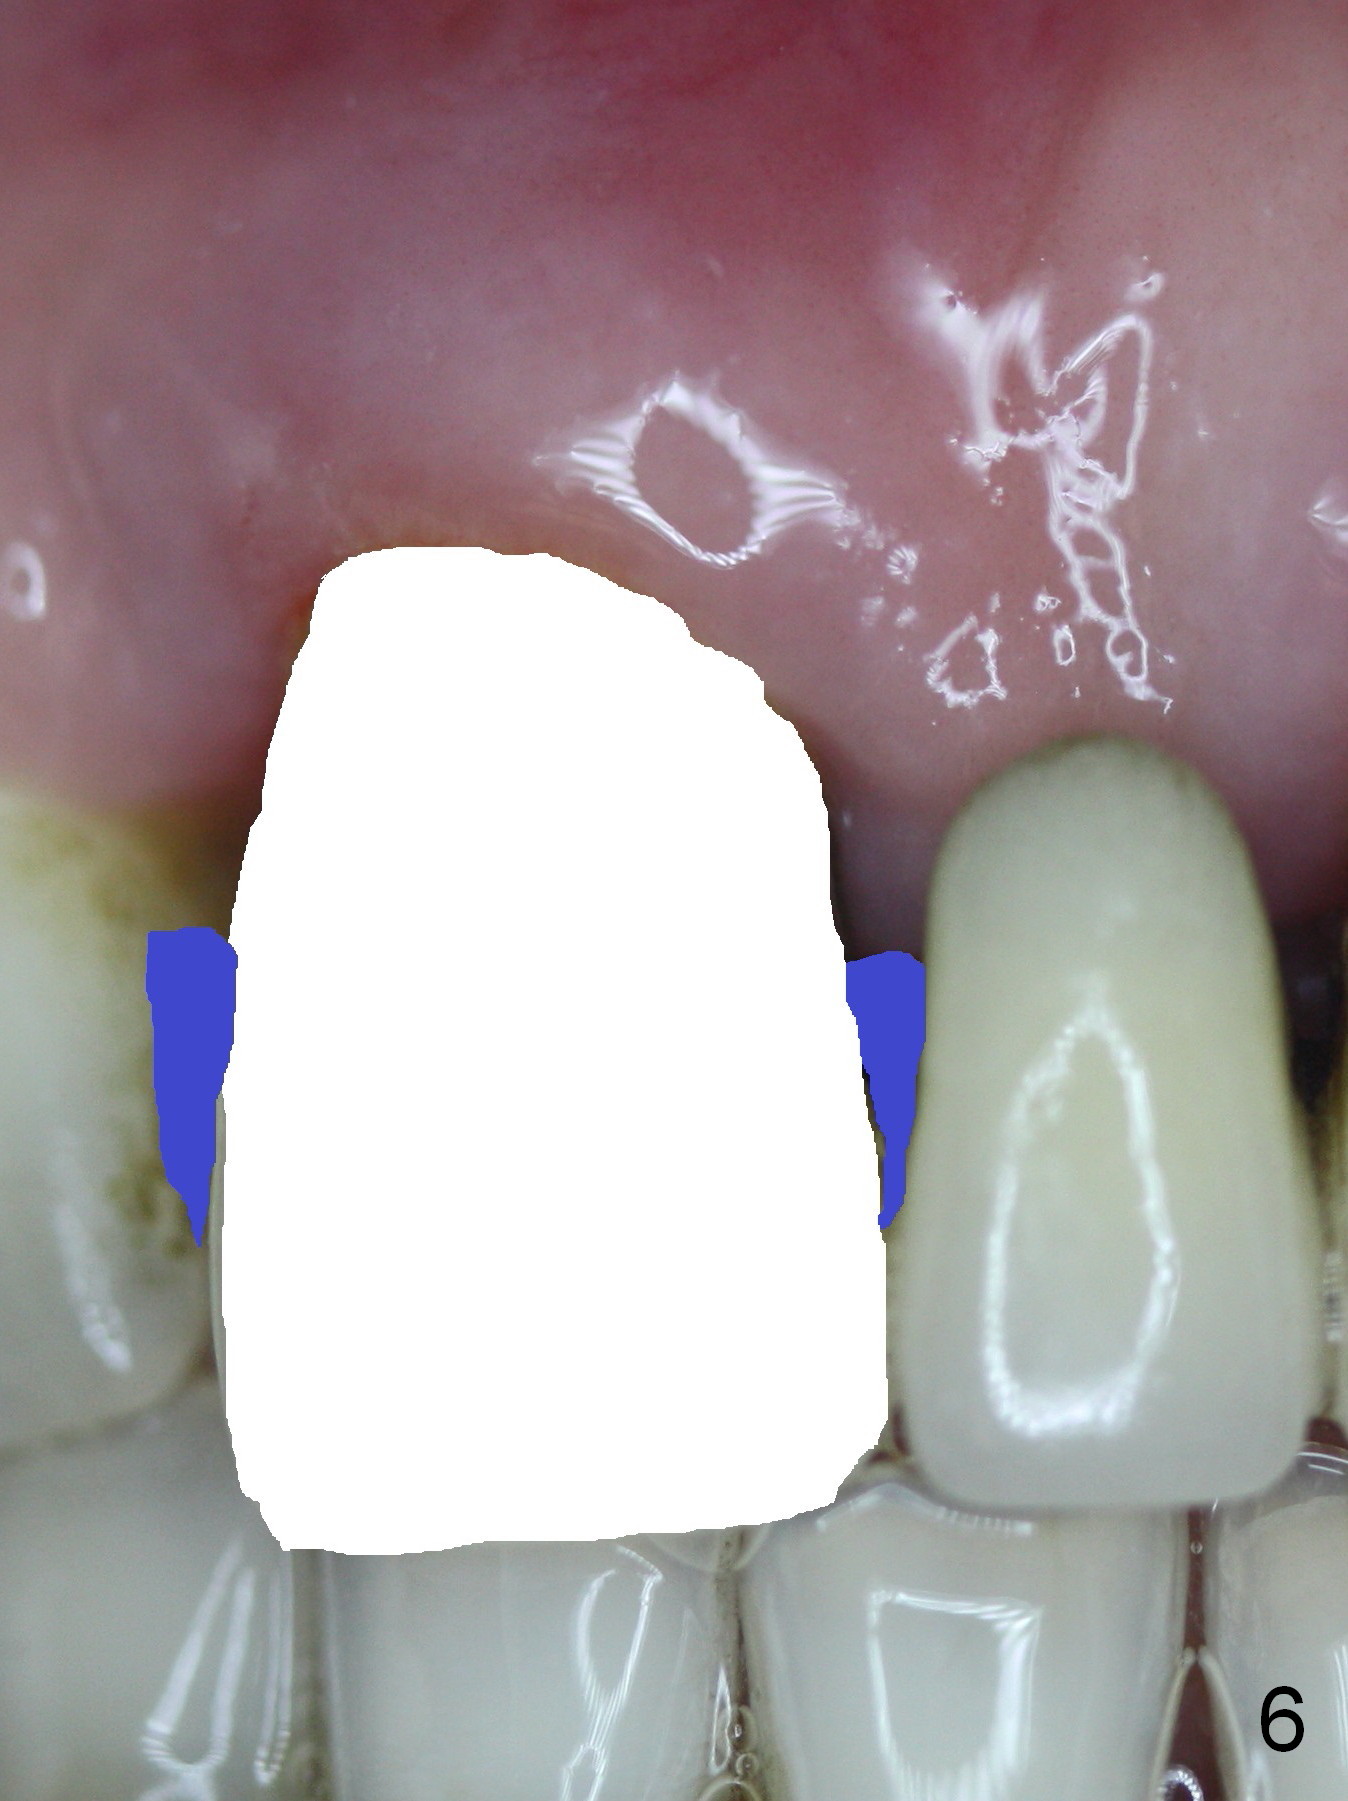

The 74-year-old patient is excited about having 3 implants placed without discomfort (1,2). He wants to take care of a loose FPD spanning from #8 to 9 (Fig.1). It appears that #8 is non-salvageable (Fig.2 * with deep pockets). There is severe bone loss around the affected tooth (Fig.3; Osteotape is expected for buccal and lingual defects). In addition, the Incisive Canal is abnormally large (arrowheads). The coronal end of a 4.5x20 mm implant and a 3.5x5 mm abutment will be slightly deviated mesially (Fig.4), since the 3-unit FPD will be converted to 2 single unit crowns. Surgical guide is ready. The 1st step is to section between #8 and the pontic (Fig.5; green outline: implant; red: abutment). If primary stability is low, the immediate provisional (Fig.8 white area) will be bonded the tooth #7 and the pontic as a supplementary measure (blue areas). Once the implant is osteointegrated, the distal portion of the pontic (Fig.7 *) will be removed. Acrylic is added to the mesial portion of the provisional (Fig.8 *) so that the papilla (P in Fig.7) will be pushed mesially and incisally (Fig.8 arrowheads). The step will be repeated a few weeks later (Fig.9). It could be done bilaterally at the same time by removing #9 crown and converting to the provisional. Finally the pontic will be removed. Two relatively wide crowns will be fabricated if the patient is satisfied with the provisional.